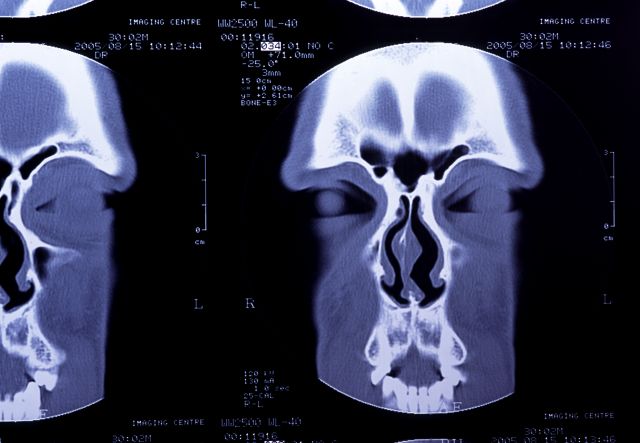

副鼻腔CT検査は、X線を使い鼻や副鼻腔の状態を立体的な3D画像で確認できる検査です。副鼻腔レントゲンよりも詳細に見ることができ、治療計画や手術前の評価に役立ちます。